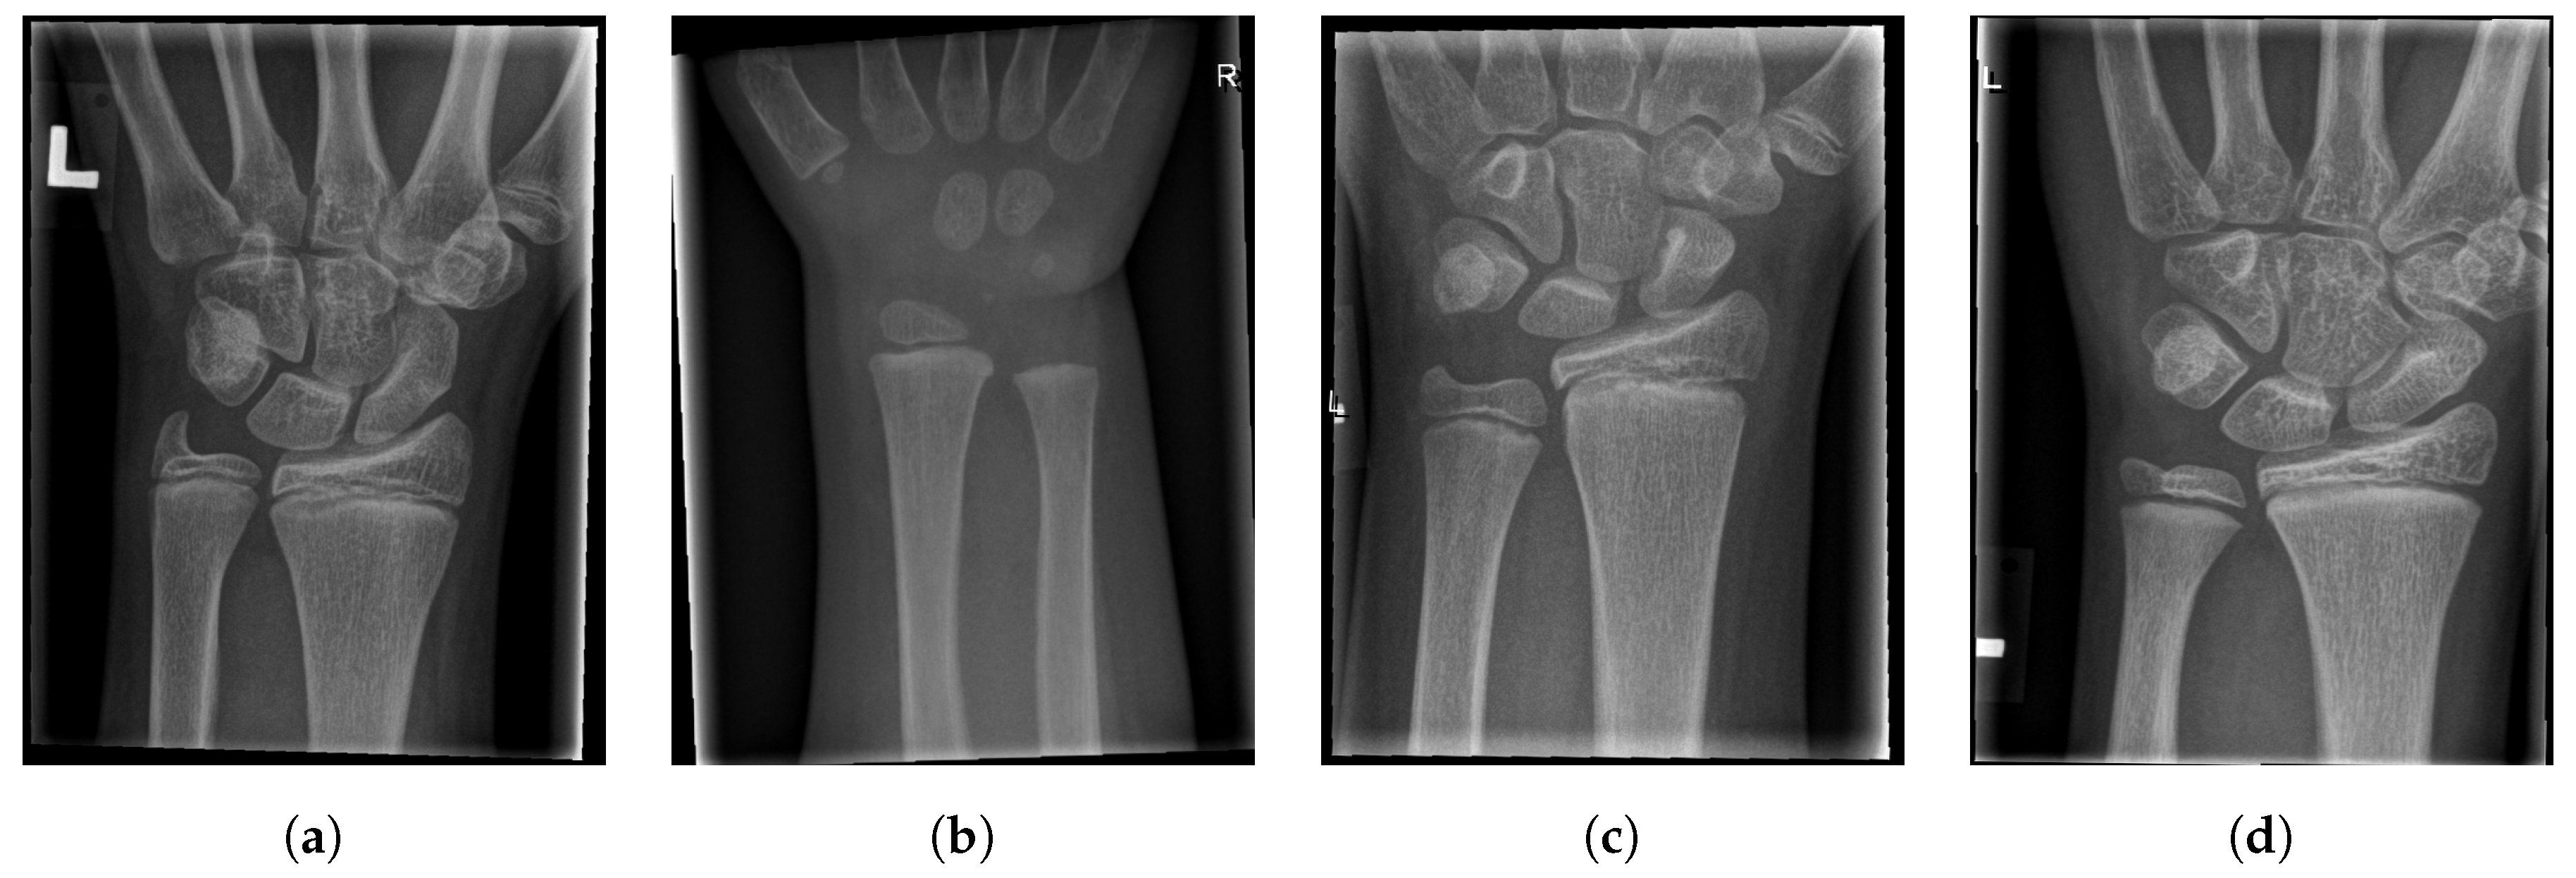

- True Negative (TN): The case when the image does not contain a fracture and the algorithm did not mark it as fractured.